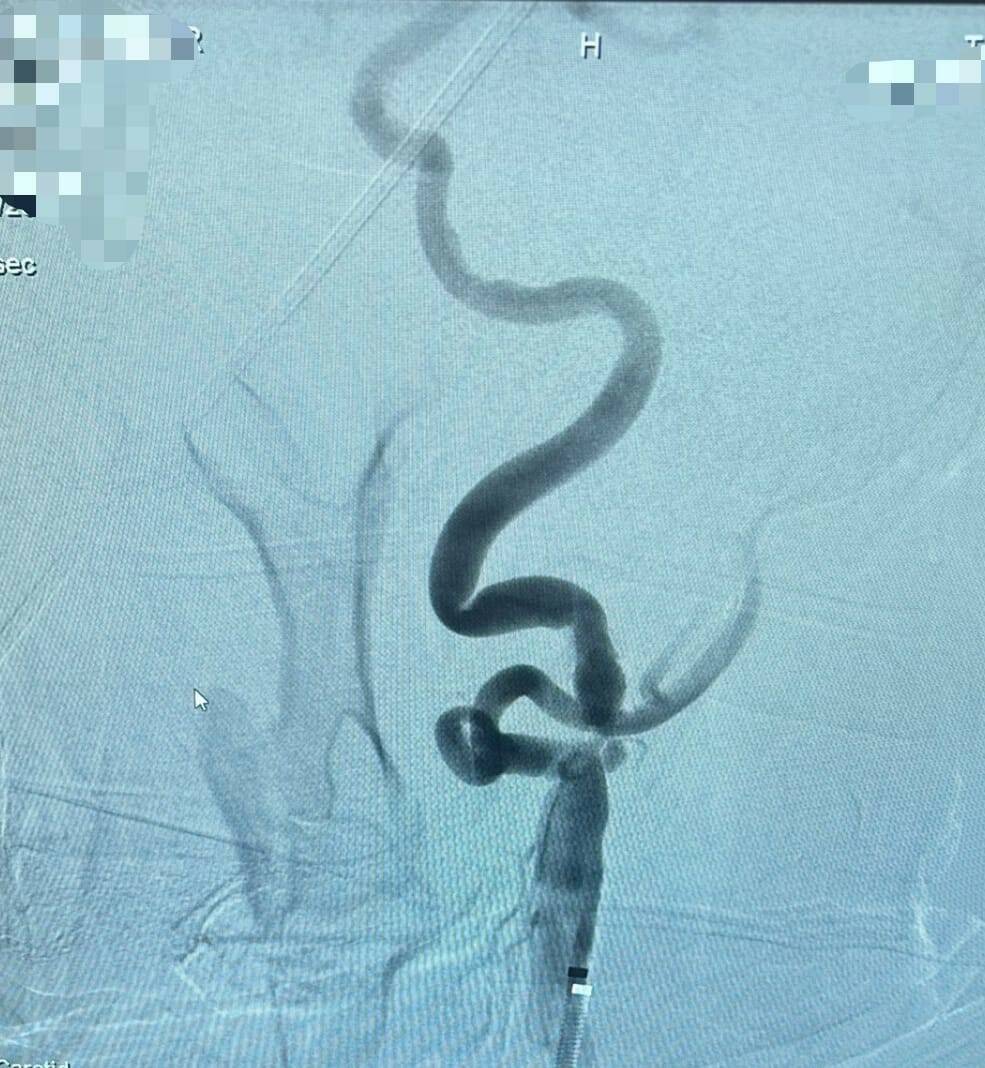

Kastamonu Eğitim ve Araştırma Hastanesi Girişimsel Radyoloji Ünitesi, önemli bir tedavi yöntemini daha uygulamaya başladı. Beyne giden şah damarlarında oluşan darlık ve plaklara karşı uygulanan stent tedavisi, artık Kastamonu’da da yapılmaya başlandı. Bu sayede felç (inme) riski taşıyan hastalar, büyük şehirlere gitmeden, kendi memleketlerinde tedavi olabilecek.

Girişimsel radyoloji, vücut içindeki damarlara ve organlara görüntüleme cihazları eşliğinde ulaşılarak yapılan, çoğu zaman ameliyatsız şekilde uygulanan tedavileri kapsar. Bu birimde şimdiye kadar, akciğer kanaması (pulmoner hemoptizi) geçiren hastalarda kanamayı durdurma, bağırsak damarlarında (mezenterik arter) gelişen tıkanıklıklarda tekrar kan akımını sağlama gibi hayat kurtaran müdahalelerin yanında, tümör tedavileri, diyaliz kateteri yerleştirme, abse boşaltma gibi pek çok önemli işlem başarıyla gerçekleştirildi. Son olarak girişimsel radyoloji tedavilerine şah damarı stentleme işlemi de eklendi.

Kastamonu Üniversitesi Tıp Fakültesi Dahili Tıp Bölümü aynı zamanda Kastamonu Eğitim ve Araştırma Hastanesi Girişimsel Radyoloji Uzmanı Dr. Öğretim Üyesi İsmail Taşkent, “Şah damarı darlıkları felç riskinin en önemli nedenlerinden biridir. Bu müdahale artık hastanemizde güvenli ve etkili şekilde uygulanıyor. Böylece hastalarımız şehir dışına gitmeden, bu önemli tedaviye burada ulaşabiliyor” dedi.